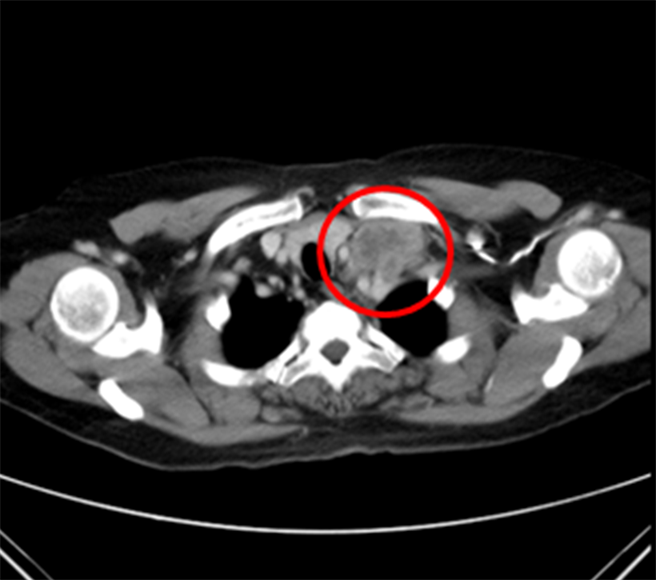

治疗后,颈部肿瘤2x1公分。(童综合医院提供/陈淑娥台中传真)